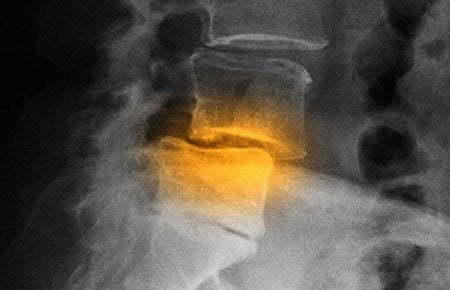

Рентгенография

Рентгенологическое исследование — самый информативный метод диагностики остеохондроза. Если врач подозревает, что причиной тахикардии стало разрушение межпозвонковых дисков, то делаются снимки в двух проекциях. На них хорошо просматриваются все рентгенографические признаки остеохондроза. Это сформировавшиеся остеофиты, уменьшение расстояния между телами позвонков, истончение дисков.

Остеохондроз на рентгене.